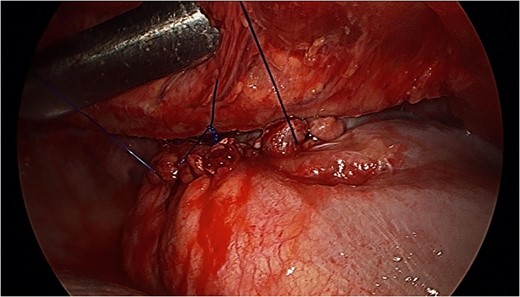

Tension-free primary suture repair of the diaphragmatic defect.

Upon reduction of the hernia, balancing the risks of recurrence and infection between primary or mesh repairs can be challenging. There is a paucity of literature to determine whether primary or mesh repair is most appropriate. Given our patient's presentation, juxtaposed with the intra-operative findings of healthy diaphragm but intra-pleural free fluid, a tension-free primary repair using a non-absorbable suture was deemed appropriate.